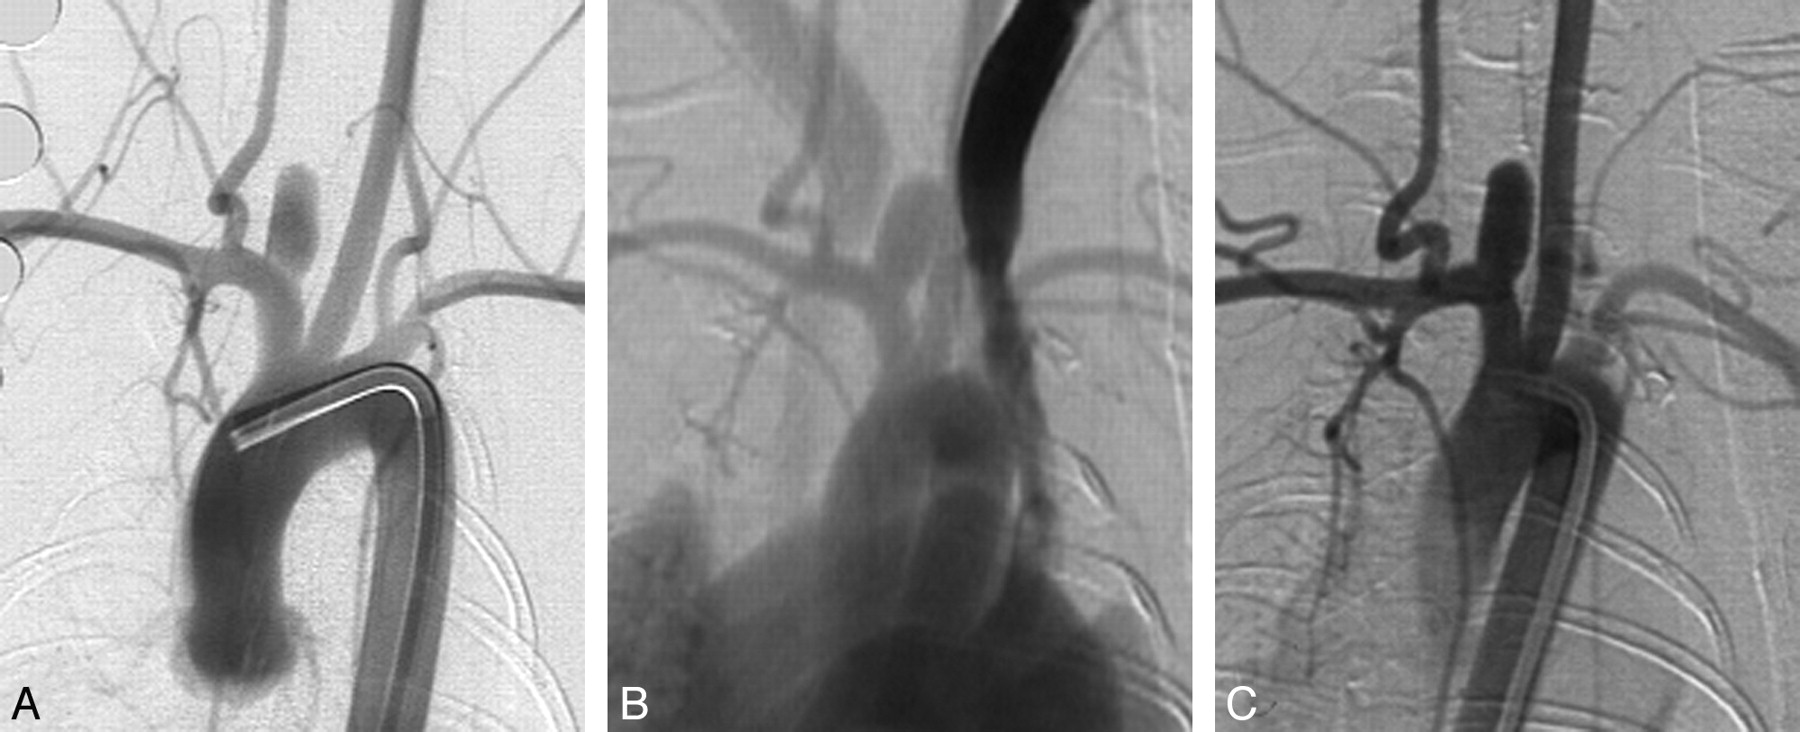

Eleven (11/12, 92%) aneurysms remained completely patent angiographically throughout the 5 years following creation (Figs 1 and 2). At 2 years, a single narrow-neck aneurysm (neck size, 1.4 mm; width, 4:5 mm; ratio of width/neck, 3:2) showed partial thrombosis (Fig 3), which remained stable at 5 years.

Serial DSA in an elastase-induced aneurysm. A, AP IADSA obtained 1 month after creation demonstrates an aneurysm cavity along the brachiocephalic artery, at the origin of the ligated RCCA. B, AP IVDSA in the same aneurysm 2 years after creation. C, AP IADSA in the same aneurysm 5 years after creation. Aneurysm dimensions remain constant throughout follow-up.